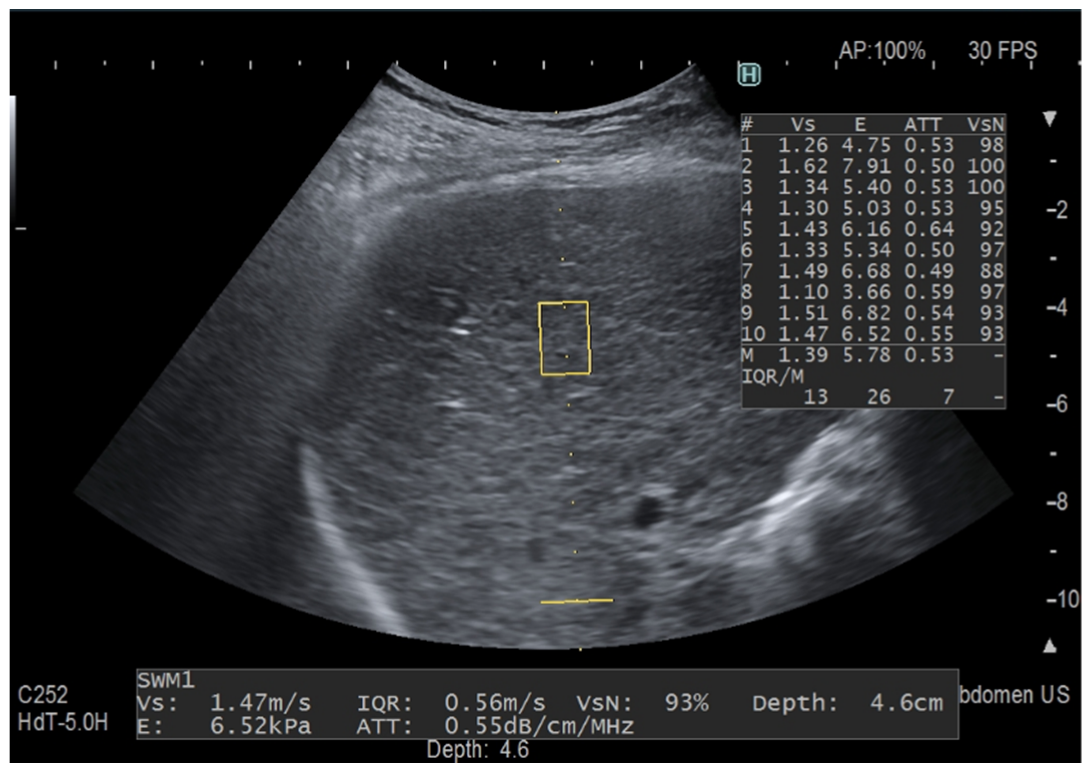

Figure 2.

Fat quantification with iATT. The two horizontal yellow lines graphically show the width (length of each line) and the length (distance between the two lines) of the iATT measurement area, which has a fixed size (length of 4 cm, from 35 to 75 mm from the skin). The measurement of the attenuation coefficient is given in dB/cm/MHz together with liver stiffness measurement. The yellow rectangle is the region of interest (ROI) for stiffness measurement. This measurement was taken in a 58-year-old patient with primary biliary cirrhosis but not steatosis.